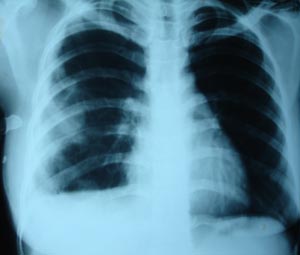

Hydropneumothorax

The air fluid level is to be marked. Fluid in pleural cavity assumes a different shape. In the presence of pneumothorax. In this case the edge of the lung is difficult to see on the PA view. Causes of pneumothorax includes emphesema, trauma, tuberculosis, pulmonary fibrosis or metastasis.